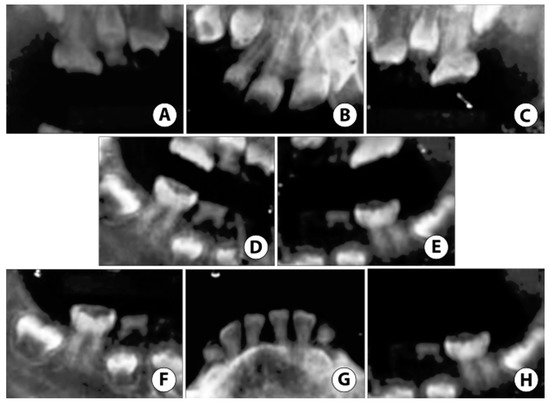

Due to prior ineffective OCS and severe ASD, treatment under General Anesthesia (GA) was accepted as the best method to restore the patient’s oral health. Under GA, a full set of radiographs were taken (Figure 5), along with intraoral photographs (Figure 6), which revealed an irregular/extensive caries pattern extending to the cusp on all permanent first molars due to attrition and poor enamel to dentin strength associated with DGI-II. The patient had amber-hue colored anterior teeth with most enamel missing and attrition down to the gingival margin on all primary first and second molars, and caries were present on the facial surface of all upper and lower anterior incisors as seen in Figure 6.

Figure 5.

Case 2: Non-digital radiographs taken in the hospital under General Anesthesia (GA) reveal (A–C) severe enamel loss with reduced pulp space in both primary and permanent teeth. (D,E) Root tip fragments of upper primary canines noted. (F,H) Extensive atypical occlusal caries noted on lower permanent first molars. (G) Reduced pulp space in permanent mandibular incisors with near exfoliation of lower primary canines.